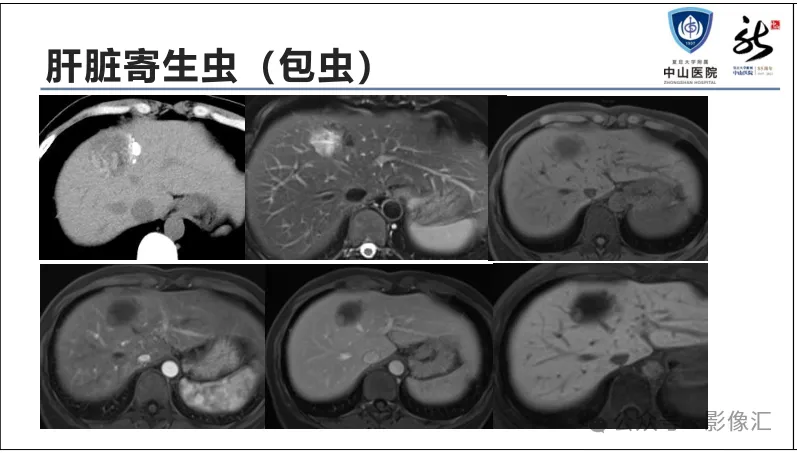

肝胆特异性对比剂增强肝胆图像判读方法与策略,课件来源于网络,作者复旦大学附属中山医院放射科饶圣祥教授。